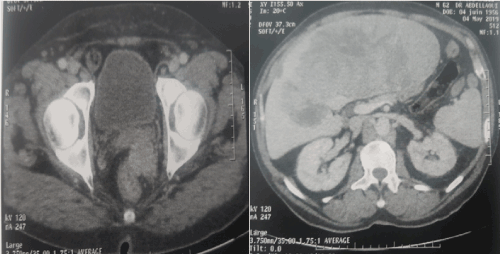

A 63 years old man with history of diabetes and hypertension, presented for bone pain. Pelvic X Ray showed multiple osteoconsensant lesions of the iliac wings, the sacrum and the femurs (Figure 1). CT scan objectified multiple hepatic metastases with a laterorectal mass (Figure 2). Colonoscopy showed aspect of extrinsic compression. Endoscopic ultrasound objectified a rectal mucosal lesion of 5x3,5 centimeters appearing in contact with the prostate (Figure 3) [1-5]. Histologically, hepatic biopsy confirmed a tumor proliferation that was made of two architectural aspects independent cells, and trabeculolobular classical endocrine architecture with expression of synaptophysin on immunochemistry [1-5] (Figure 4).

Figure 1. Pelvic X Ray showed multiple osteoconsensant lesions of the iliac wings, the sacrum and the femurs